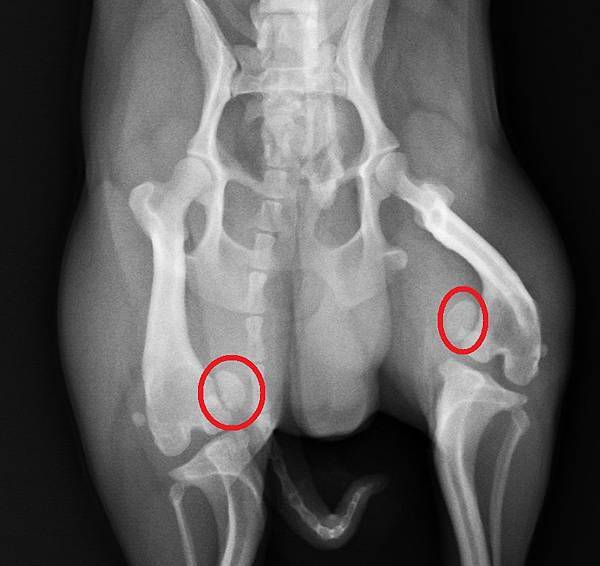

紅圈圈內的是膝蓋骨

應該要在大腿骨遠端與骨頭重疊(請自行摸著膝蓋比對~)

一個是真的有膝關節四級異位的,可以看到膝蓋骨跑到大腿關節內側